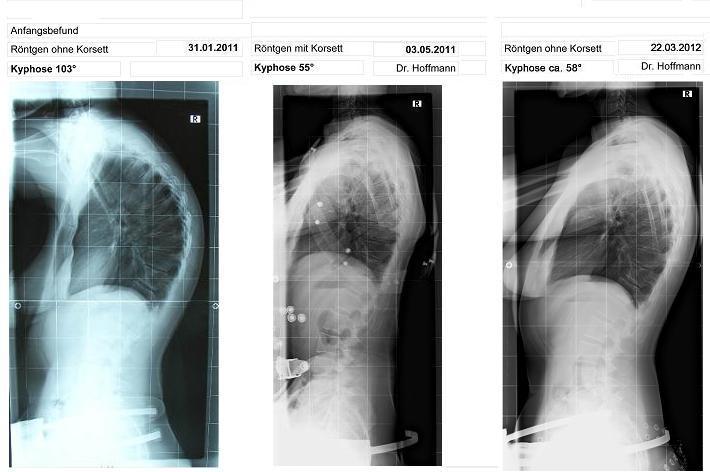

auf dem linken Bild die 103 Grad ohne Korsett -

auf dem mittleren Bild 55 Grad im Korsett -

und im rechten Bild 58 Grad nach ca. 3 Stunden ohne Korsett und 3 Wochen wenig Tragezeit

ich denke, die Gradzahlen sind ungefähr gleich geblieben. Die drei Grad liegen ja auch in der Messtoleranz, ich habe mir auch gerade überlegt, ob das mittlere Bild nicht mit dem rechten identisch ist, aber sowas lässt sich auch noch schnell korrigieren, wenn es wirklich die gleichen Bilder sind. Aber wenn man von den Ausgangswerten ausgeht, ist das schon eine beachtliche Leistung, eine Hyperkyphose von 103° auf 55°, bzw. 58° runter zu korrigieren. Daran sieht man, dass die WS trotz Erwachsenenalter noch beweglich ist. Solche Ergebnisse sollten so schnell wie möglich veröffentlicht werden, damit auch die Fachleute davon überzeugt werden, dass ein korsett bei Erwachsenen was bringt.

anbei der aktuallisierte Röntgenvergleich.